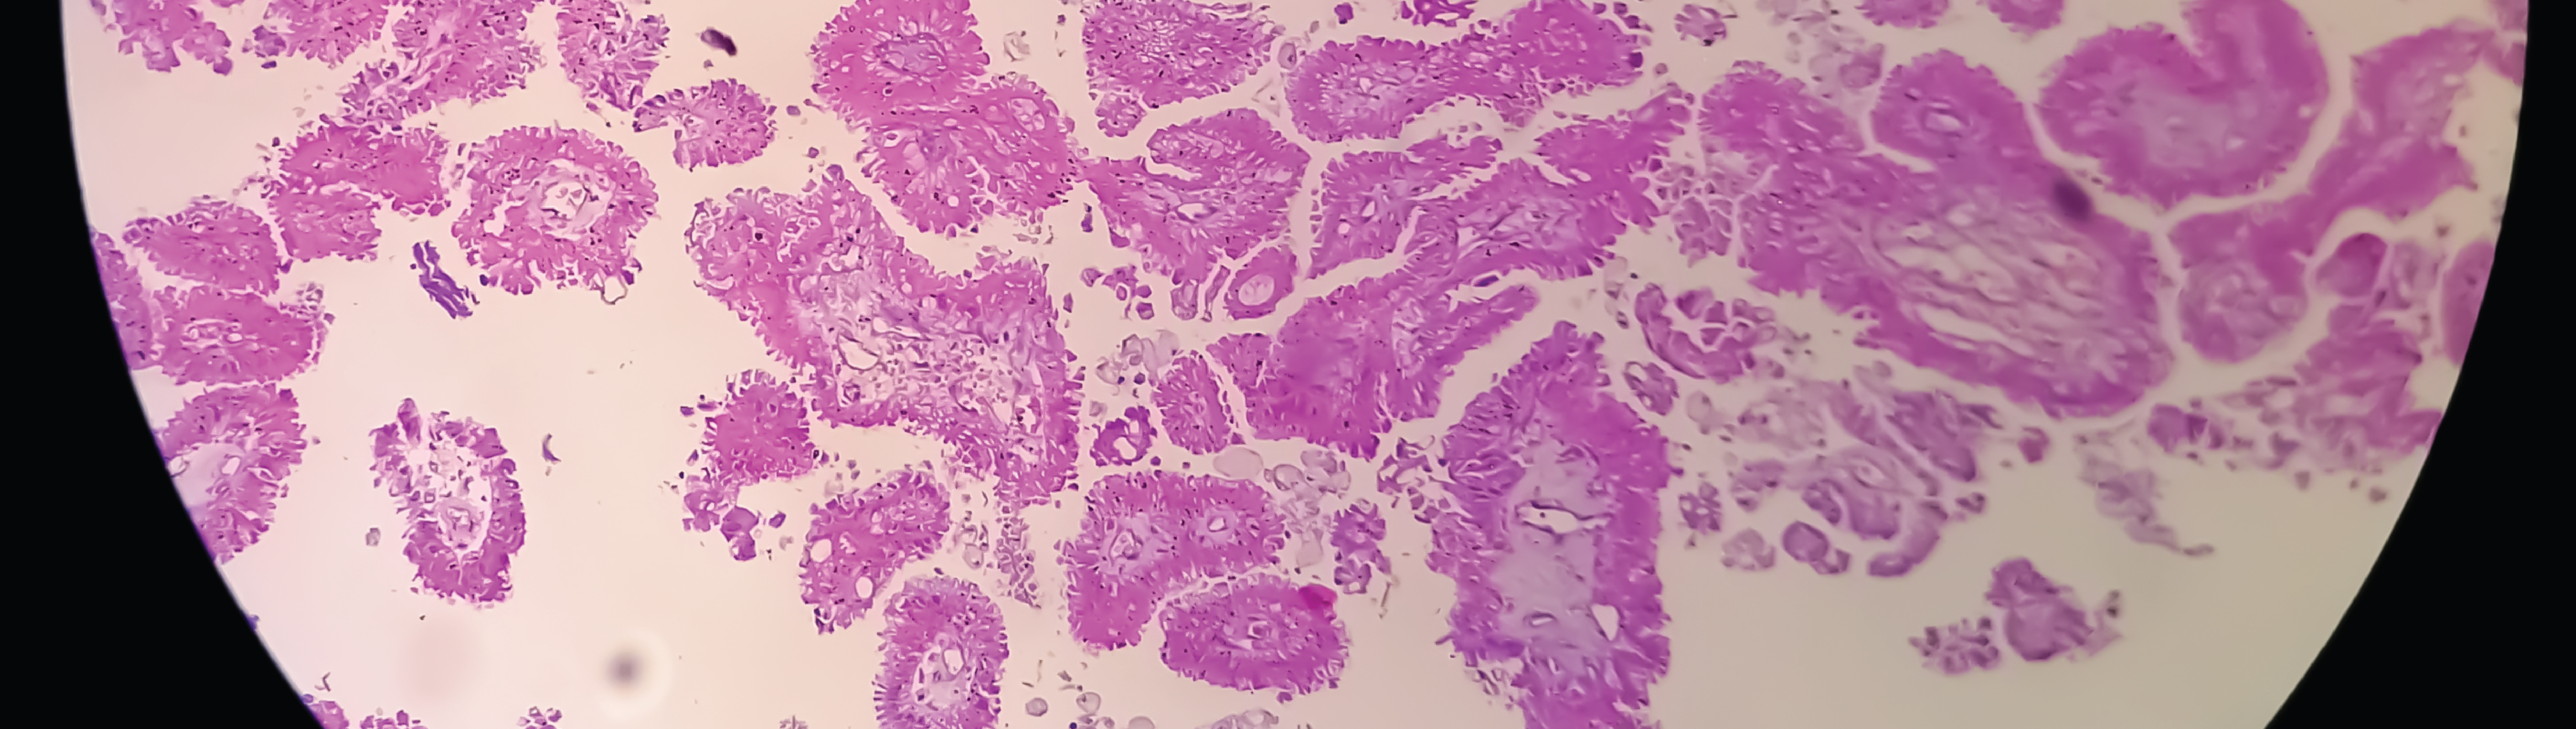

Over 80% of the tumors identified in this younger cohort were invasive.

The study further notes a higher-than-expected number of hard-to-treat subtypes, including triple-negative breast cancer (TNBC), which disproportionately affects younger women and is associated with rapid progression and fewer therapeutic options.